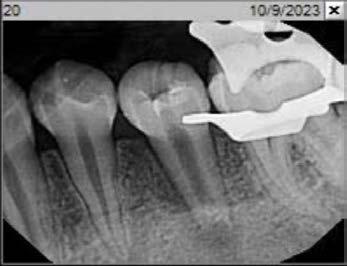

Cover: It’s a tricky situation. Patient with partial denture

Technique for extracting tooth or root tip from underneath fixed partial denture emphasizes use of magnification from dental loupes or dental surgical operating microscope for precision when performing technique-sensitive procedure. Case report.